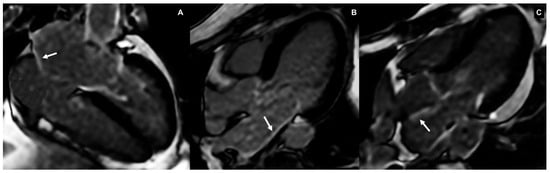

3.2.3. Left Atrial Tissue Characterization